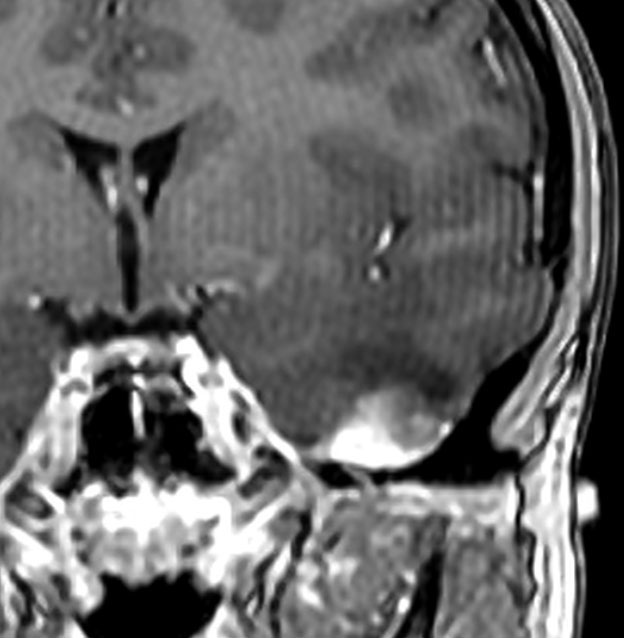

脳幹部から発生した退形成性神経節膠腫 grade 3

軽い右顔面神経麻痺で発症した小児で,右上下肢の軽度の失調症もありました。脳幹部(橋)の右背側から発生した腫瘍で,軽度の閉塞性水頭症を合併しています。左はT2強調画像で,橋の右側ににじむような浸潤像と浮腫があります。腫瘍は小嚢胞を形成してT2強調画像で実質は等信号です。真ん中の画像はCISS画像で橋が腫大しているのがよくわかります。右側はガドリニウム増強像で,全体が増強されてまだらな増強所見となっています。正中後頭下開頭で全摘出 gross total removal して,局所放射線治療とtemozolomide, cisplatine, etoposide, gleevec, hydoreaなどの化学療法を行いましたが,手術後4ヶ月で激しい播種再発を来しました。